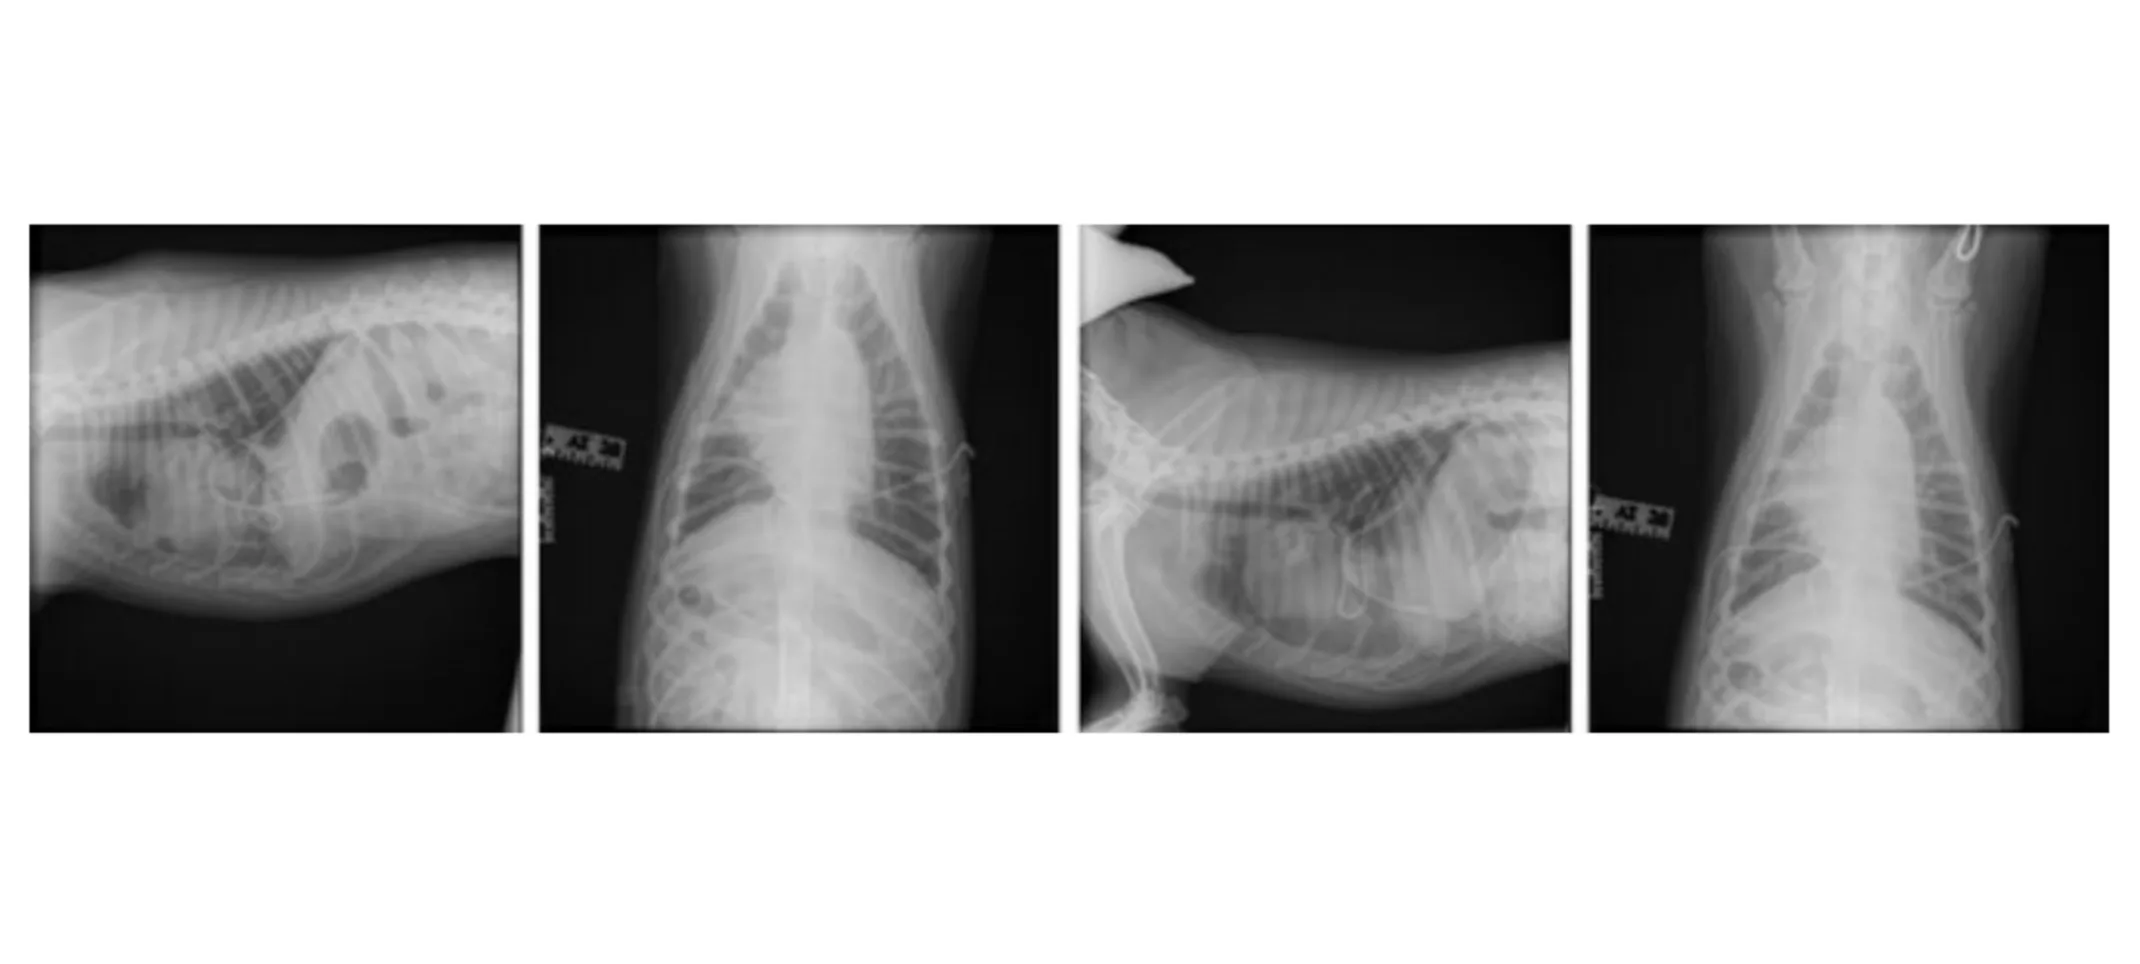

Radiographs (05-28-2024):

Findings: Mild residual pleural effusion, small amount of pleural air, presence of chest tubes

Interpretation: Post-chest tube placement with no primary intrathoracic lesions identified